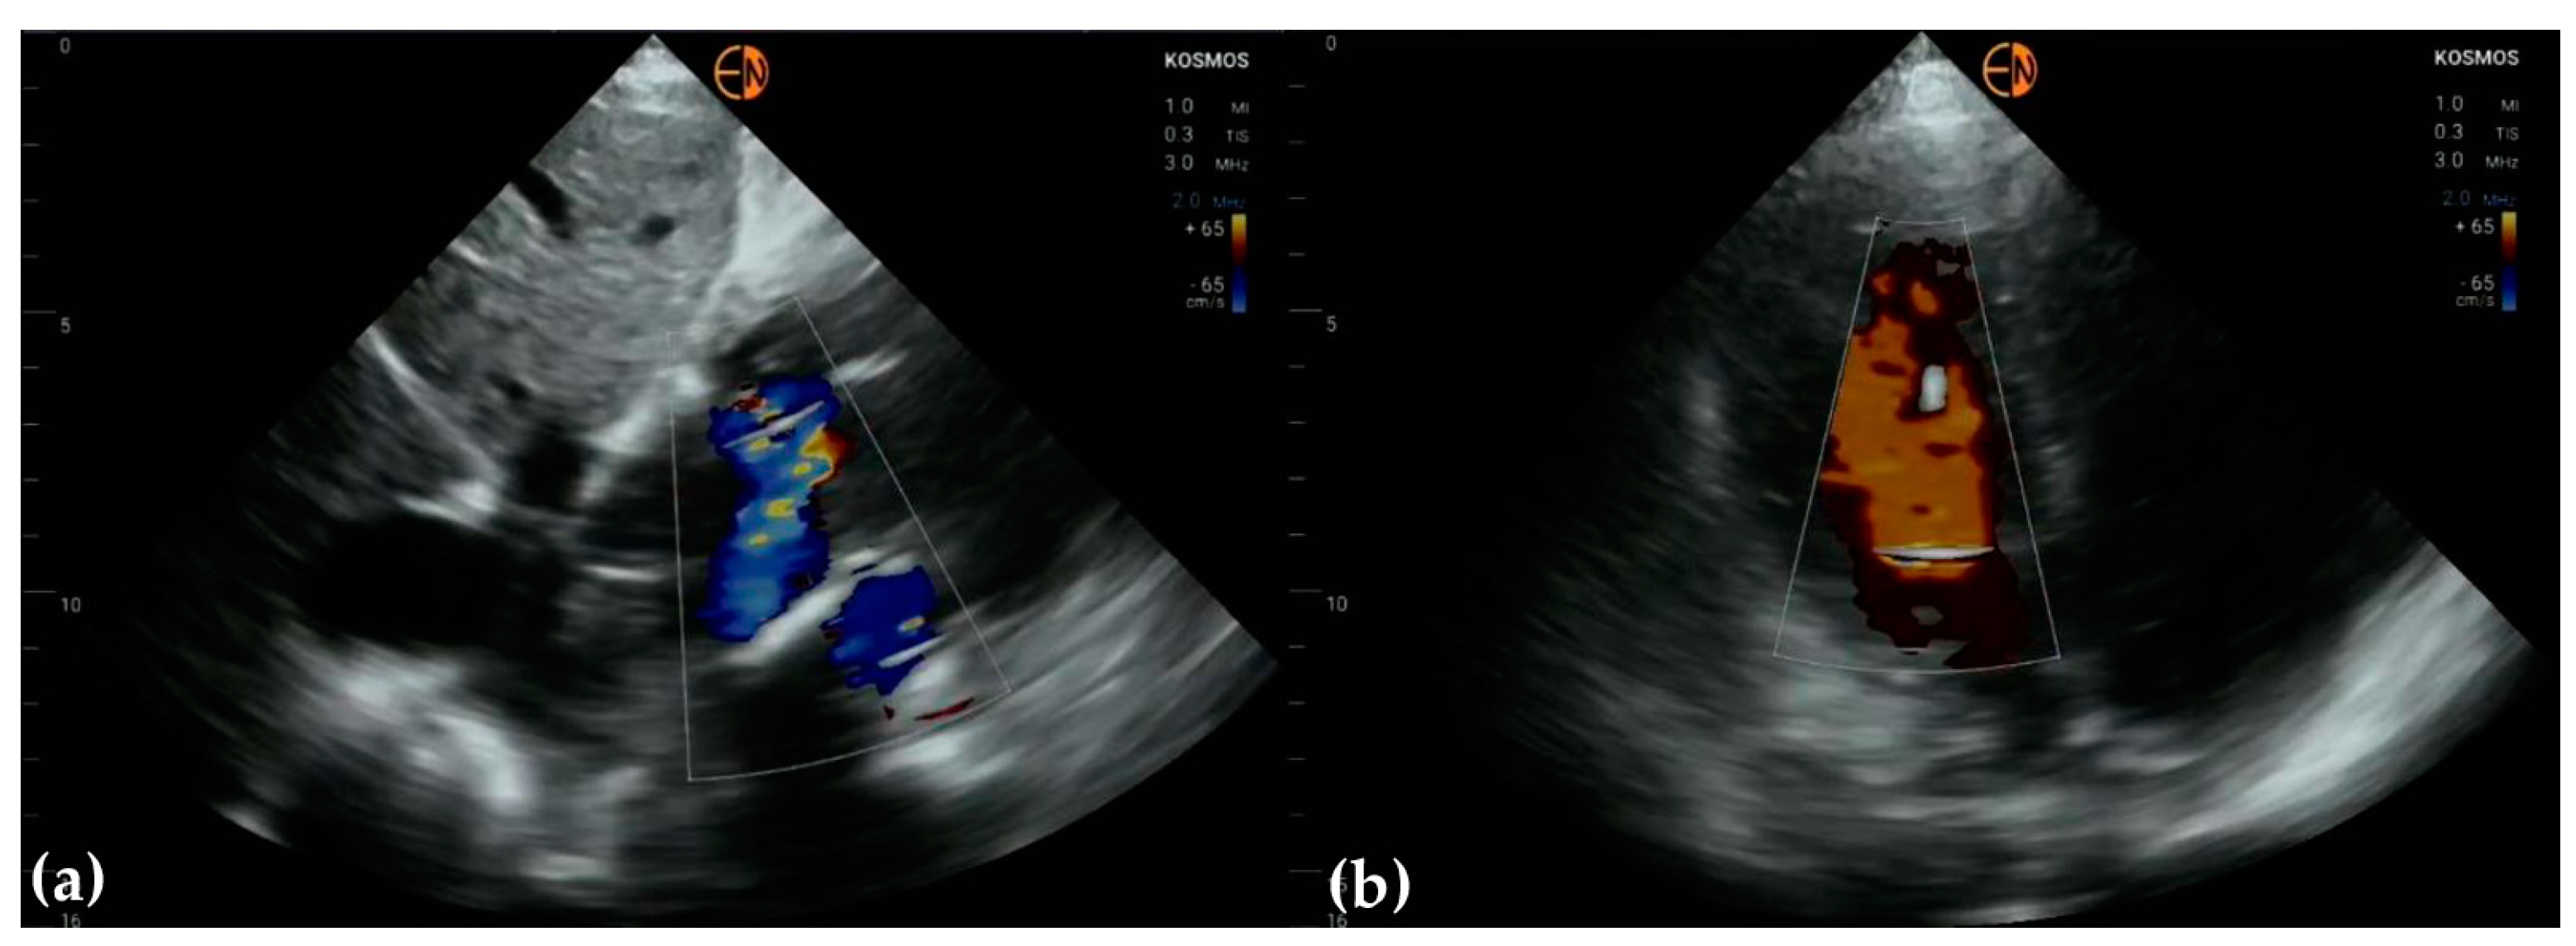

3.3. Valvular Stenosis and Regurgitation

| Mitral valve | 26 (61.9 [45.7 to 76.0]) 0.5321 [0.3451 to 0.7191] | ||

| Mild mitral regurgitation | 16 | 14 | |

| Moderate mitral regurgitation | 10 | 7 | |

| Severe mitral regurgitation | 1 | 1 | |

| Normal | 15 | 21 | |